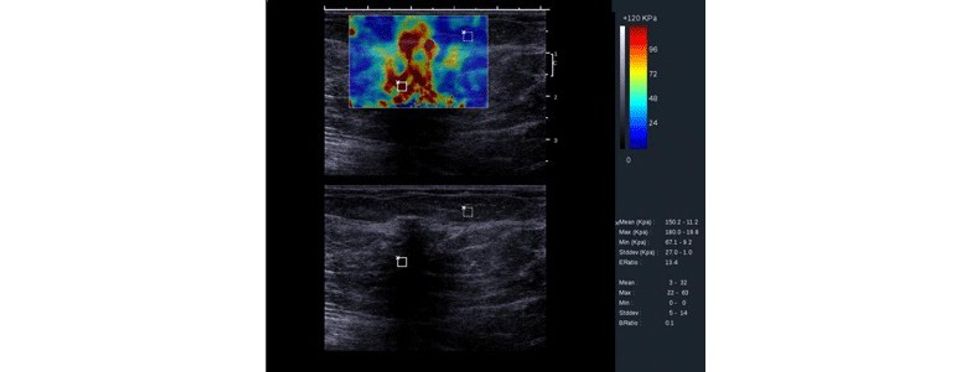

Të dhënat e fituara përpunohen përmes paketës softuerike në formë të color mapping apo grayscale për të vizualizuar zonën me interes e cila ekzaminohet.

Parimet bazë te elastografisë bazohen në dukurinë që indet nën kompresion shfaqin tendosje dhe kjo do të paraqitet me karakteristika të ndryshme. Prandaj, nën kompresion, në boshtin aksial, duke bërë matjet, mund të vlerësohet ngurtësia dhe elasticiteti i indit, para dhe pas kompresionit, ndërsa imazhi i paraqitur dhe i llogaritur quhet elastogram, ku fushat me ngurtësi të rritur dhe elasticitet të ulur paraqiten me ngjyrë të kaltër.

Me aplikimin e elastografisë krahas ultrazërit konvencional, mundësohet që të rritet specificiteti i ultrazërit, sidomos në lezionet e kategorizuara me BiRads 4, duke bërë përcaktimin e elasticitetit të indit, detektim të qartë të nivelit të elasticitetit të indit dhe, marrë parasysh që formacionet me natyrë malinje kanë dendësi më të lartë dhe elasticitet të ulur gjatë aplikimit të kompresionit në boshtin aksial e shprehur në kPa. Pastaj me anë të mapingut qartë detektohet natyra e lezionit.